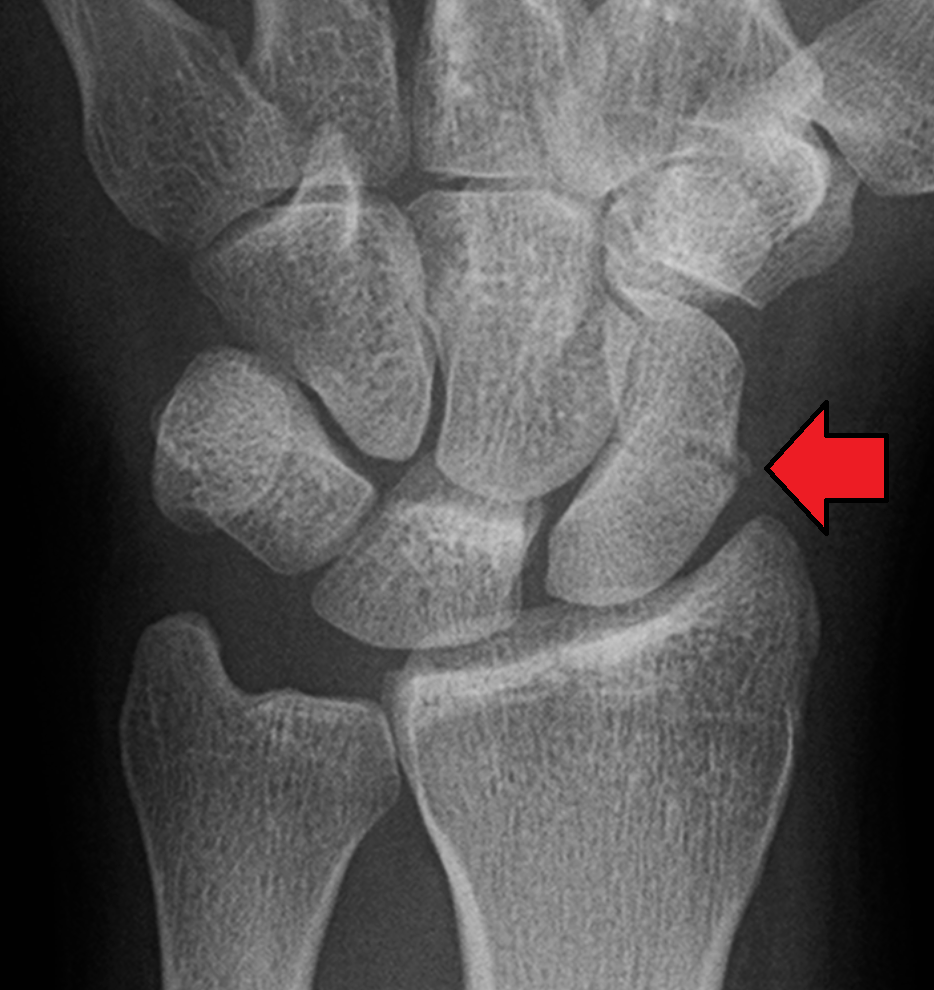

Example 4

Diagnosis

Fracture of the medial epicondyle

Example 5

Scaphoid fracture